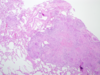

Is there a pathology present in this picture?

If so, what is it?

Sarcoidosis: well-formed granulomas